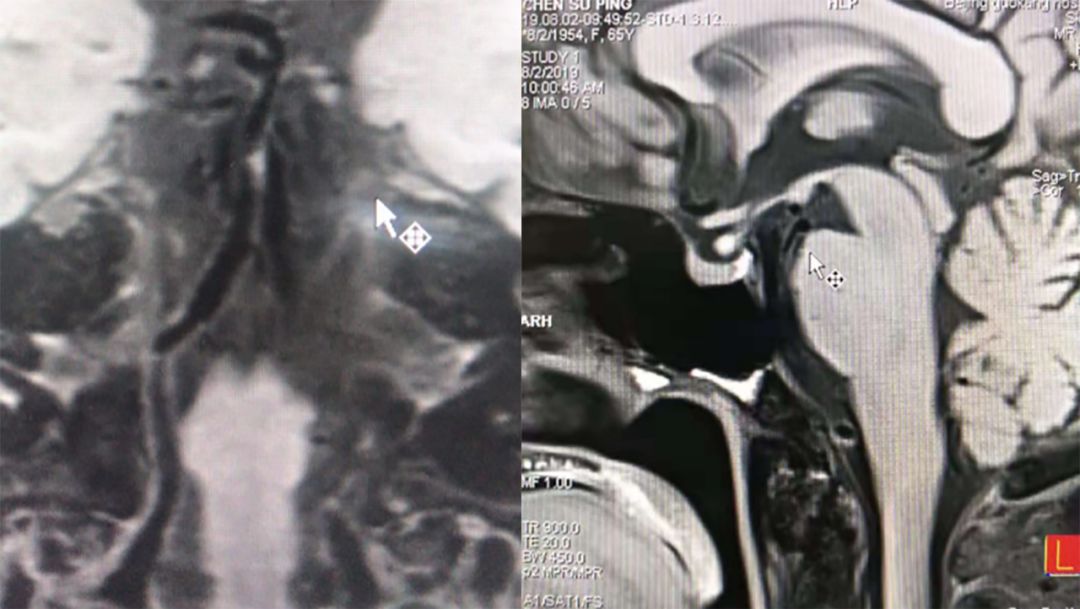

脑MRI (2019-6-18 ,*** 人民医院):右侧桥脑急性脑梗死(图1)。

图1

高分辨磁共振(北京**医院,2019-8-2):怀疑基底动脉夹层可能性大(图5)。

图5